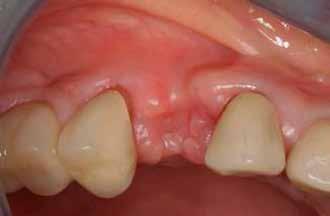

Kiindulási helyzet

A páciens egy 56 éves nőbeteg, nem dohányzik, általános egészségi állapota jó (ASA I), gyógyszert nem szed, ismert allergiája nincs. Fő panasza, amellyel klinikánkat felkereste, hogy elégedetlen mosolyával. Elmondása alapján az utóbbi években krónikus gyulladás alakult ki frontfogai körül, amely érezhető mobilitáshoz vezetett. Ez a probléma jelentősen befolyásolta a magabiztos beszédben és étkezésben. A páciens hosszú távú megoldást keresett, de aggódott a kezelések alatt fellépő esetleges fájdalom miatt. Az extraorális vizsgálat során megállapítottuk, hogy a mosolyvonal közepesen magas és a frontfogak torlódottak (1–2. ábrák). A szájüregi vizsgálat során a 1.2, 2.1 és 2.2 fogak körül előrehaladott parodontális tapadásveszteséget és mobilitást találtunk (3. ábra). A CBCT (cone beam CT) felvételen látszott, hogy a 2.1 fog bukkális csontfala hiányzik (4. ábra).

3. ábra: Az intraorális vizsgálat során a bal felső nagymetszőnél és mindkét oldali kismetszőnél parodontális tapadásvesztést és mobilitást találtunk.

A második szextánst akrilát ideiglenes híddal láttuk el (7. ábra). A sebgyógyulást követően a 2.1 fognak megfelelő területen a gerinc horizontális és vertikális csonthiánya volt megfigyelhető (8. ábra).

A fogeltávolítást követő hathetes kontroll alkalmával zavartalan sebgyógyulást tapasztaltunk (9. ábra). Gerincéli metszésből teljes vastagságú lebenyt preparáltunk az implantátumok behelyezéséhez. Az implantátumok helyének előkészítéséhez Straumann® Cassette sebészi szettet használtunk. Ezt követően a 1.2 fog helyére egy 3,3 mm átmérőjű, a 2.1 fog helyére pedig egy 4,1 mm átmérőjű Straumann® Roxolid® SLActive® BLT implantátum került (10. ábra). Az implantátumokat a sebészi kézidarab segítségével 15 fordulat/perc sebességgel és 35 Ncm nyomatékkal helyeztük be. Ezzel egyidejűleg a 2.1-es pozícióban lévő implantátum

6. ábra: A bal felső nagymetszőt és a két kismetszőt eltávolítottuk, majd a jobb felső nagymetszőt és a szemfogakat előkészítettük. – 7. ábra: Akrilát ideiglenes híd. – 8. ábra: A gyógyulást követően horizontális és vertikális csonthiány látszik a bal felső nagymetsző területén. – 9. ábra: Hat hónappal a fogeltávolítást követően: a gyógyulása zavartalan volt. 10. ábra: A 1.2 helyére egy 3,3 mm átmérőjű, a 2.1 helyére pedig egy 4,1 mm átmérőjű Straumann® Roxolid® SLActive® BLT implantátum került. – 11. ábra: Öt hónappal a beültetést követően kontrollröntgen készült a 2.1 implantátumról, amelyen ellenőriztük az implantátum megfelelő pozícióját és integritását.